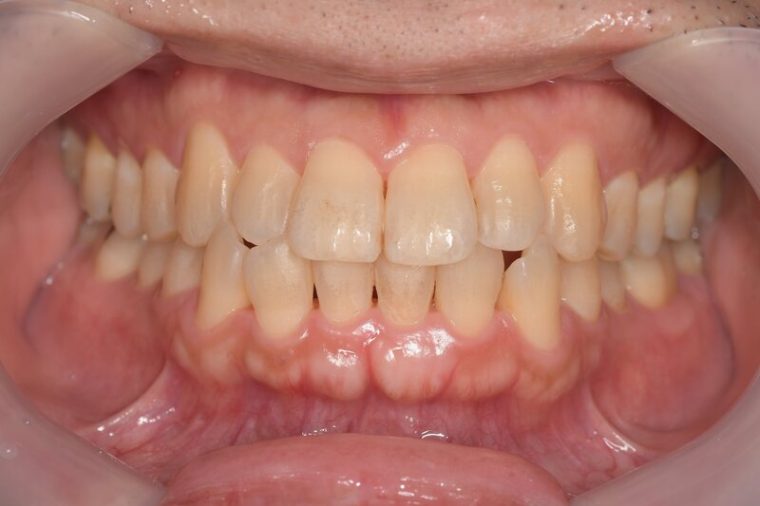

中等度歯周病

特徴

歯肉炎~歯周炎の段階です。

• 腫れや歯磨きの時の出血が頻繁に起こる

• 歯はグラつかない、もしくは少しグラつく

• 口臭がある

• 歯ぐきがムズムズする感じがある

• 歯周ポケットが深くなる

• 歯の周囲組織の破壊が始まる

中等度歯周病の歯ぐきの写真

治療内容

歯科医院で深くなってしまった歯ぐきの溝の中にある汚れを専用の器具で除去する必要があります。溶けてしまった骨は一般的には元通りに戻りません。歯ブラシの毛先を当てて磨くことで一時的に症状が治まることがあります。歯周病は慢性的に進行することが多く中程度歯周病の場合、進行を防ぐため歯科医院と相談しながら定期的にクリーニングを受けるようにしましょう。